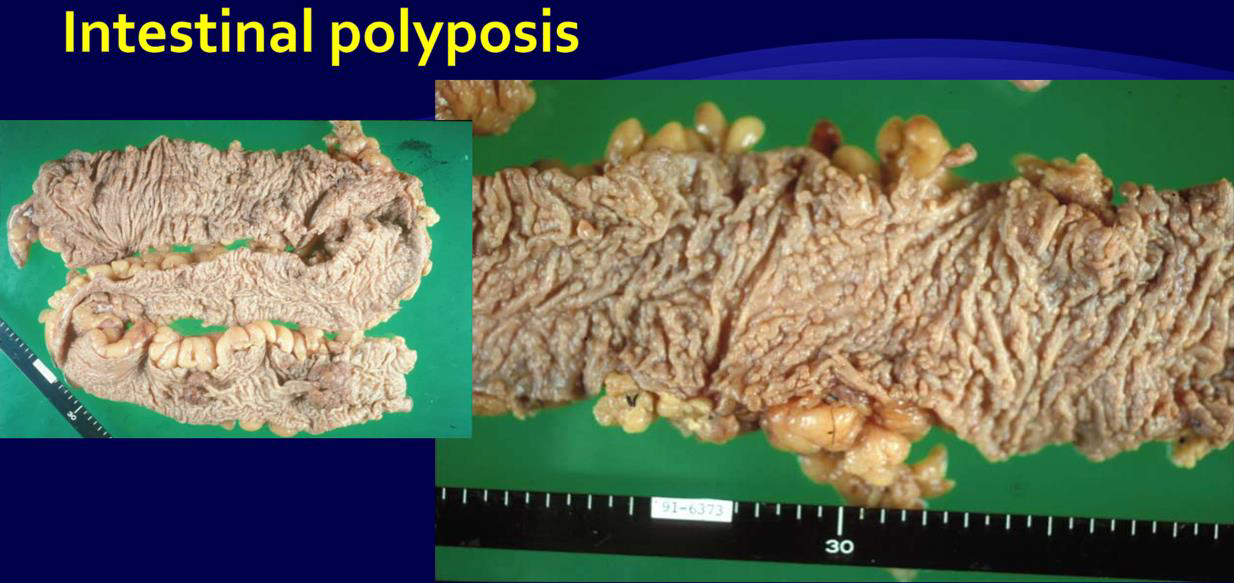

Peutz-Jeghers syndrome

- 體染色體顯性

- STK11/LKB1

- peri-oral跟oral cavity會出現很多pigment

- 惡化腸道癌症intestinal cancer 15被 → 預防性切腸子